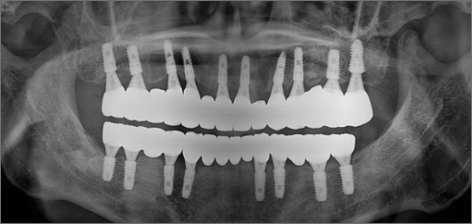

초진 : 2014.06.13

치료 후 : 2016.10.14

THE 이해승치과에서 2014년에 치료 받으신 40대 환자분의 사례입니다. 흡연과 음주가 근본 원인이 되어 2014년 전악 임플란트 치료를 받으셨습니다. 감사하게도 저희와 함께 꾸준히 8년간 관리를 동행하시며 추가적인 전신 질환 없이 건강한 50대를 보내고 계십니다. 치료 경험을 통해 변화를 만드신 환자분을 존경합니다.